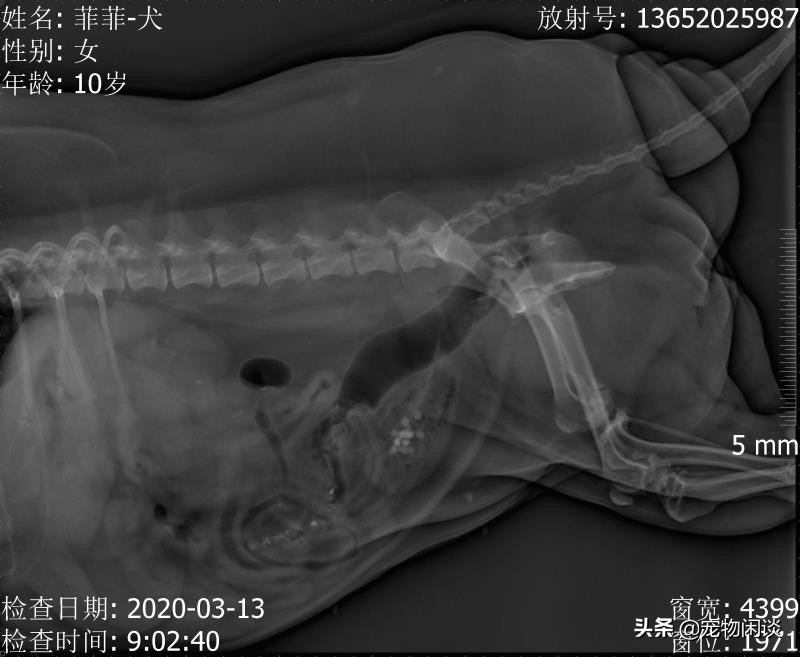

菲菲的X光

临床诊断:该宠物有尿血症状,触诊发现阴部有肿块,X光显示子宫有轻微扩张,膀胱有结石,肾脏也有发现结石,血常规,C一CRP显示有较高炎症,生化肾脏指标明显升高

临床确诊:膀胱结石,肾结石,子宫扩张,阴部肿块待检